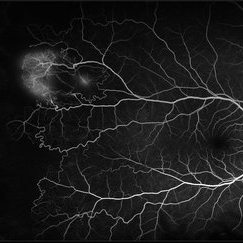

Sickle cell retinopathy (Proliferative) (2 files)

Sickle cell retinopathy (Proliferative) (2 files)

Proliferative sickle retinopathy (1 file)

Proliferative sickle retinopathy (1 file)

Proliferative Sickle Cell Retinopathy (Stage3) (10 files)

Proliferative Sickle Cell Retinopathy (Stage3) (10 files)

Sickle Cell Retinopathy (11 files)

Sickle Cell Retinopathy (11 files)

Sickle Cell Retinopathy SC (6 files)

Sickle Cell Retinopathy SC (6 files)

Sickle Cell (1 file)